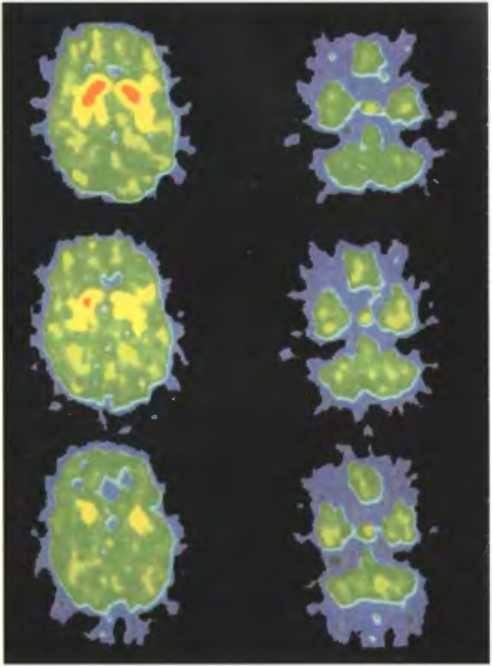

Кокаин вызывает у человека эйфорию, блокируя рецепторы в клетках мозга, которые в норме удаляют избыток дофамина. Это приводит к повышению концентраций дофамина, возбуждающего участки мозга, влияющие на настроение. На верхней паре томограмм показаны уровни поглощения дофамина в норме (красный цвет — высокий уровень поглощения, желтый — средний, зеленый — низкий).

Вверху: после приема плацебо. В середине: после приема низкой дозы кокаина (o,1 мг на кг массы тела). Внизу: после приема высокой дозы кокаина (о,6 мг на кг массы тела). В последнем случае дофамин почти не связывается и воздействует на другие нейроны намного сильнее, чем в норме.